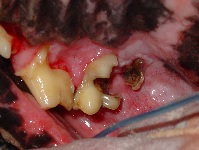

A 5-year-old Cocker Spaniel is presented for a routine scale and polish procedure.  The dog is in good health and there is no history of inappetence.  While doing a thorough oral inspection under general anaesthesia, you see the following pathology.

a) The right maxillary 1st (109) and 2nd (110) molars.

b) Caries (tooth decay), Resorptive lesions, Crown fractures.

In cases as depicted on the photo, there is marked crown destruction as well as pulp exposure and extraction of the tooth is the only treatment available.